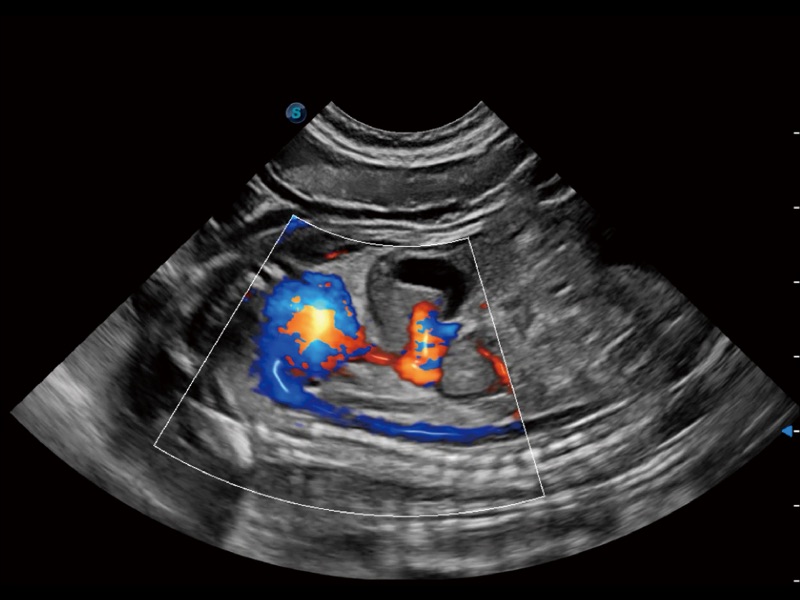

• Micro F 显微血流成像

通过创新的 Matrix E自适应滤波器和超长时间域算法,极大提升超低速微细血流的检出能力,同时更精准地滤除软组织和噪声信号,为兽用医生提供以往无法通过常规血流获得的疾病诊断信息。

(犬)左室长轴血流

(犬)髂动脉血流

(犬)胎儿主动脉弓立体血流